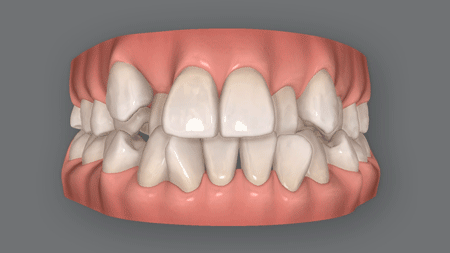

開咬とは?

オープンバイトとも呼ばれる開咬(かいこう)は、奥歯で噛んだときに上下の前歯閉じず隙間空いてしまう症状です。